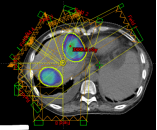

病例展示三:胰腺癌

腺癌病灶压迫并侵润十二指肠,十二指肠梗阻不能正常进食,患者留置营养管及胃肠减压管;伴胆道梗阻诱发黄疸,留置PTCD引流管。诊断:1.胰头恶性肿瘤 cT4N0M0 III期 KPS评分:80分;2.十二指肠不全梗阻;3.梗阻性黄疸,4.心律失常 室性期前收缩5. 慢性心力衰竭6.陈旧性心肌梗死7.冠状动脉粥样硬化性心脏病8. 缺血性心肌病。治疗:2024-05月开始吉西他滨+白蛋白紫杉醇化疗4周期,碳离子放疗剂量:PTV 36Gy(RBE)/9fx,后缩野补量,剂量:PTV boost 18Gy(RBE)/4fx,4.5Gy(RBE)/fx。

疗效评价